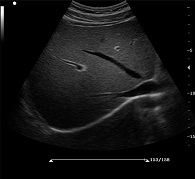

? ? ? ?C7為深圳安盛生物醫(yī)療技術(shù)有限公司新一代便攜式彩超產(chǎn)品,采用了先進(jìn)的PC平臺(tái),擁有強(qiáng)大的處理能力,優(yōu)異的圖像性能,集小巧輕便、全面的功能與輕巧流暢、特有的U型設(shè)計(jì)與一身,提供大眾新選擇。

? ?● PHI脈沖反相組織諧波成像+頻率復(fù)合技術(shù)

? ? ? ?保證良好穿透力的同時(shí)獲得更加細(xì)膩的二維圖像

? ?● 空間復(fù)合成像技術(shù)

? ? ? ?通過(guò)多個(gè)角度圖像復(fù)合減弱單一圖像偽像,提高信噪比